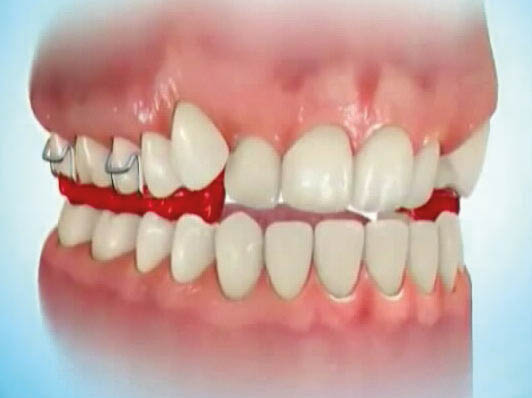

وقتی یک دندان در کراس باشد (شکل 26-5) میتوانید برای فک پائین یک اسپلینت آکریلی بسازید و چند براکت روی دندانهای بالا بچسبانید و به کمک یک سیم 0.012 سوپرالاستیک قدامیهای بالا را پروترود کنید تا از کراس خارج شوند (شکل 27-5 الی 28-5).

شکل 28-5: قراردادن سیم نازک سوپرالاستیک 0.012 برای پروترود شدن انسیزورها و اسپلینت آکریلی متحرک پائین جهت باز کردن بایت